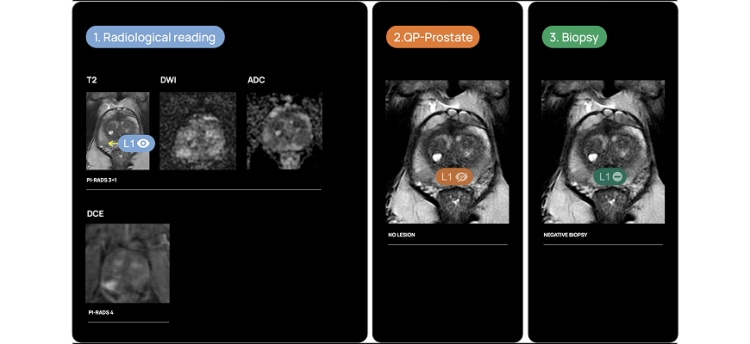

Clinical Case 03.

69 yo biopsy patient with PSA: 5 ng/ml.

THE RADIOLOGIST DETECTS 1 LESION:

-L1(PI-RADS3 DCE+, PIRADS 4)

QP-PROSTATE DETECTS O LESION:

-L1 No lesion.

TARGETED BIOPSY CONFIRMED O LESION:

-L1 Benign Prostatic Tissue.